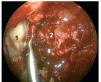

Caso clínico: Varón de 42 años de edad con paresia del VI par craneal derecho y estudios de imagen mediante resonancia magnética y tomografía computarizada craneales sugestivos de displasia fibrosa esfenoclival. Se lleva a cabo un abordaje endonasal expandido transpterigoideo completamente endoscópico, obteniéndose una amplia descompresión de las estructuras vasculonerviosas de la base del cráneo. Durante el procedimiento se utiliza neuronavegación y el canal vidiano como referencia anatómica fundamental de la carótida en su segmento lacerum.

Discusión: El AEE transterigoideo es una técnica segura y con amplio sustento en la literatura científica. En manos adecuadas, podría reducir la morbilidad asociada a los abordajes transcraneales clásicos, ya que permite un máximo potencial resectivo sobre las lesiones a tratar, con una mínima distorsión sobre las estructuras craneofaciales circundantes. Para su realización se utilizan referencias anatómicas claves como el agujero y canal del nervio vidiano. La indicación de tratamiento quirúrgico en los casos de DF de base craneal ha de establecerse en función de la presencia de sintomatología.

Case report: A 42-year-old male with right sixth cranial nerve palsy. Cranial MRI and CT showed a central skull base lesion with diagnostic suspicion of FD. Patient underwent a full endoscopic transpterygoid EEA, achieving a wide skull base neurovascular decompression. Neuronavigation and the vidian canal landmark resulted mandatory during intraoperative procedure.

Discussion: The transpterygoid EEA is a safe technique consistently supported in the literature. It may reduce the morbidity associated to the classic transcranial approaches, since it permits maximum resection with minimum craniofacial distortion. The vidian hole and canal are the landmarks used to locate and avoid injury to the lacerum segment of the carotid injury. The surgical treatment indication in FD cases must be established in symptomatic patients.